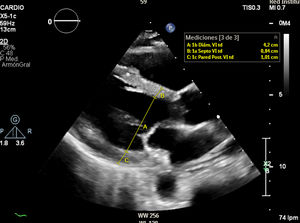

Se trata de una mujer de 41 años con deficiencia humoral y gammapatía monoclonal IgG lambda, que acude al servicio de Urgencias con fiebre y debilidad, siendo diagnosticada de infección respiratoria secundaria a Influenzae A. Veinticuatro horas después ingresa en el servicio de Medicina Intensiva por hipotensión severa, con necesidad de noradrenalina hasta 0,5 ug/kg/min, hipoalbuminemia y hemoconcentración. Se estableció el diagnóstico de síndrome de fuga capilar sistémica con edema intramiocárdico. El síndrome de fuga capilar sistémica es una condición caracterizada por la fuga de plasma y proteínas al compartimento intersticial, y se asocia con gammapatía monoclonal y frecuentemente aparece después de una infección del tracto respiratorio superior, siendo el edema intramiocárdico una complicación poco frecuente. En nuestra paciente, se realizó un ecocardiograma transtorácico al ingreso, mostrando una función ventricular sistólica dentro del límite inferior de la normalidad (FEVI 50-55%), con comportamiento restrictivo, además se evidencia un engrosamiento difuso del miocardio: eje largo paraesternal (fig. 1 y vídeo A), eje corto paraesternal a nivel apical (fig. 2), y plano apical cuatro cámaras (fig. 3), probablemente secundario a edema intramiocárdico, ya que un ecocardiograma transtorácico realizado 1 mes antes mostró grosores normales, eje largo paraesternal (fig. 4). Se prescribió tratamiento con inmunoglobulinas y corticosteroides, pero lamentablemente la paciente falleció 24 horas después del ingreso debido a un shock refractario.